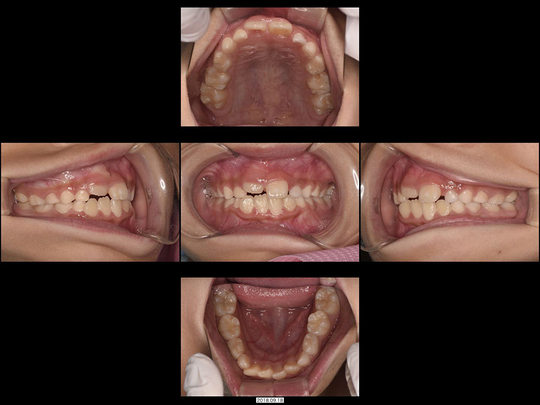

Sさん 開始時8歳 女性

矯正前

画像をクリックで拡大

矯正後

上下の前歯がガタガタでお悩みのお子さんです。

スタート時は1期治療前半の時期で、精査の結果、あごの骨年齢も実年齢と変わらないことが分かりました。そのためワイヤー矯正なし、通常通り固定式拡大装置を用いた非抜歯矯正で対応しました。

治療の期間・回数

36か月、36回

​費用

576,400円